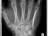

Röntgenbilder